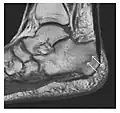

Figure 7: Fatigue fracture of the talus in a 25-year-old male basketball player with right hind foot and ankle pain, without history of trauma, and a normal initial radiograph (not shown). (a) One-month followup lateral radiograph shows normal appearance. (b) Sagittal T1-weighted MRI shows an irregular fracture line (arrow) within an ill-defined area of hypointensity corresponding to bone marrow edema.[1]

Figure 10: Calcaneal fatigue fracture in a 30-year-old male runner. Radiographs were normal (not shown). (a) Sagittal T1-weighted and (b) short tau inversion recovery images show a linear hypointensity (arrows) of calcaneal tuberosity within diffuse bone marrow edema, which appears as an ill-defined area of hyperintensity on a fluid sensitive pulse sequence (arrowheads).[1]